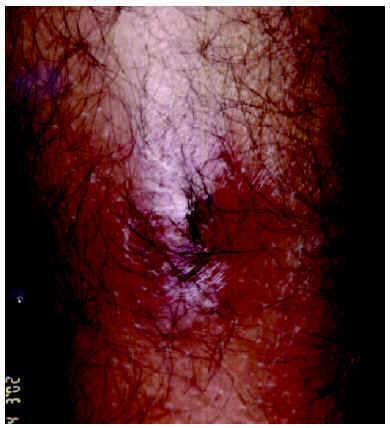

A la exploración se observaban cinco lesiones nodulares inflamatorias, con una zona blanquecina central y discreto edema periférico, localizadas en ambas piernas (fig. 1). No se palpaban adenopatías. Se efectuó expresión mecánica de una de las lesiones obteniendo una larva viva de aproximadamente 1 cm de longitud. Con la ayuda de una pinzas de disección, se extrajeron larvas similares de cada una de las otras lesiones (fig. 2). La larva fue identificada como Cordylobia antropophaga por sus características morfológicas y por su procedencia, y se recomendó tan sólo limpieza de las lesiones con un antiséptico, obteniéndose la resolución de aquéllas en pocos días.

Fig. 1.--Lesiones nodulares inflamatorias.